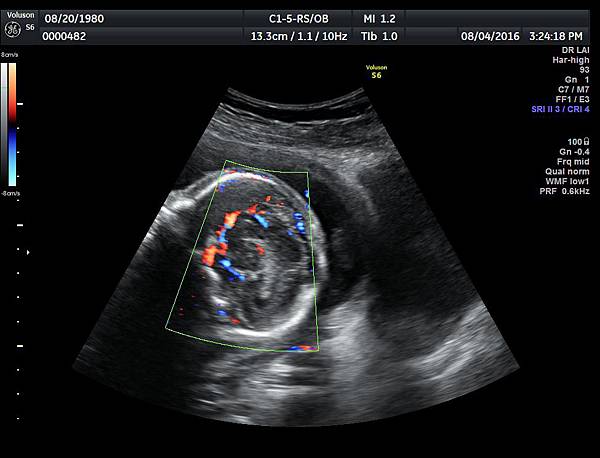

2016年8月4日在執行胎兒高層次超音波檢查時,我發現胎兒腦部的CSP(cavum septum pellucidum)很不清楚(附圖1~4),遇到這種情況,需要仔細評估胎兒腦部的駢胝體,因為CSP的天花板是駢胝體,CSP不明顯時,要合理的懷疑駢胝體沒有發育,或駢胝體下方有長東西(例如lipoma),駢胝體是連接左右大腦的神經纖維所組成。

1. 矢狀切面(sagittal plane):駢胝體呈現類似三明治的中間黑色部分,上面一層薄薄白色的區域是callosum sulcus,打上flow可以看到pericallosum artery在駢胝體上面的周圍,pericallosum artery來源是前腦動脈,參考附圖 6~10,三明治下面白白的部分是和CSP做比較得到的,如果這一層長lipoma(附圖 5),CSP很可能看不到。